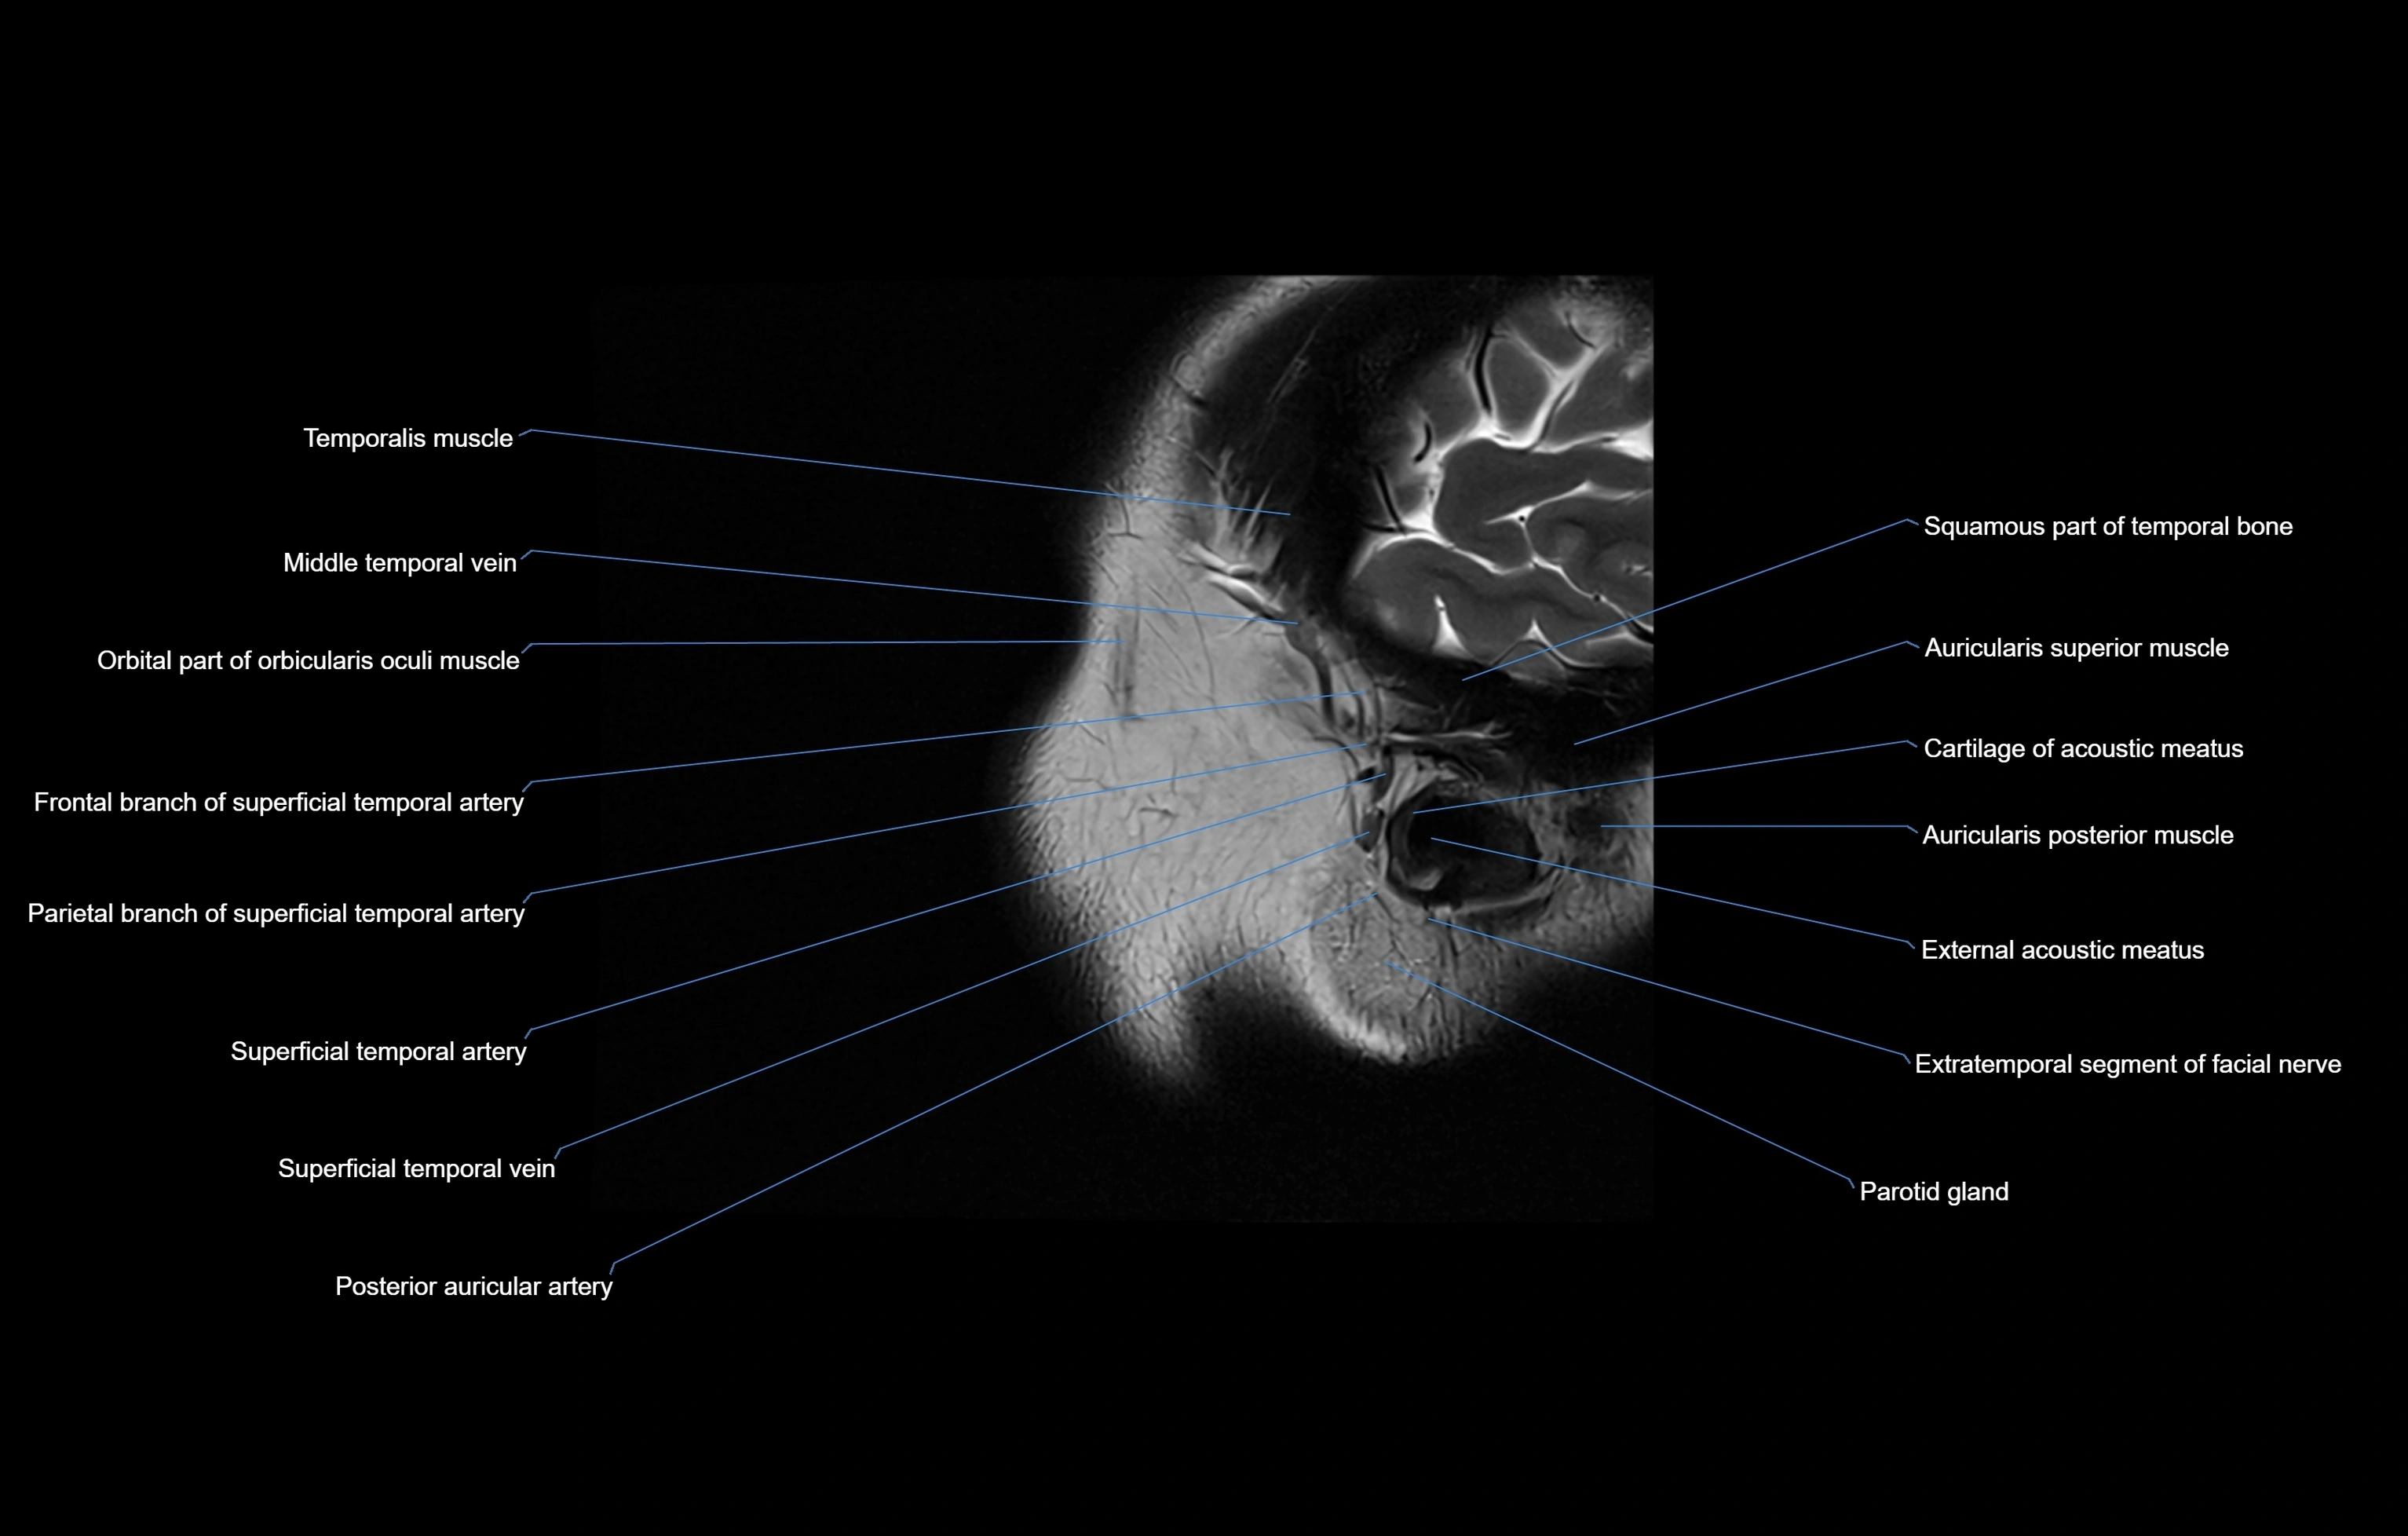

- Auricularis anterior muscle

- Auricularis posterior muscle

- External acoustic meatus

- Parotid gland

- Posterior auricular artery

- Squamous part of temporal bone

- Superficial temporal artery

- Superficial temporal vein

- Temporalis muscle